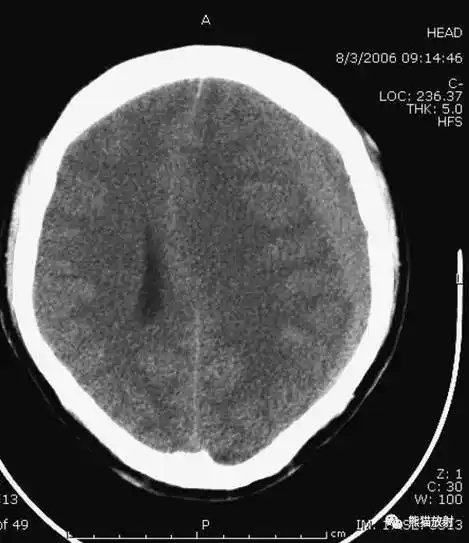

颅脑ct的正常解剖

影像总结头颅ct基本知识与常见病变

值班必备 | 急诊颅脑ct常见的八种疾病

学习这些颅脑ct图,大脑运动起来升升温吧!